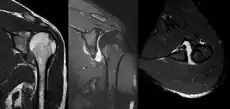

A Hill–Sachs lesion, or Hill–Sachs fracture, is a cortical depression in the posterolateral head of the humerus. It results from forceful impaction of the humeral head against the anteroinferior glenoid rim when the shoulder is dislocated anteriorly.

Diagnosis can be suspected by history and physical examination which is usually followed by imaging. Because of the mechanism of injury, apprehension of anterior dislocation is common with provocative maneuvers. Hill–Sachs lesions have been classified as "engaging" or "non-engaging", with engaging lesions defined by the ability of the glenoid to sublux into the humeral head defect during abduction and external rotation. Engaging dislocations have a higher risk of recurrent anterior dislocation, and their presence can help guide surgical management.[2] Imaging diagnosis conventionally begins with plain film radiography. Generally, anteroposterior (AP) radiographs of the shoulder with the arm in internal rotation offer the best yield while axillary views and AP radiographs with external rotation tend to obscure the defect. However, pain and tenderness in the injured joint make appropriate positioning difficult and in a recent study of plain film x-ray for Hill–Sachs lesions, the sensitivity was only about 20%. i.e. the finding was not visible on plain film x-ray about 80% of the time.[3]

MRI has also been shown to be highly reliable for the diagnosis of Hill-Sachs (and Bankart) lesions. One study used challenging methodology. First of all, it applied to those patients with a single, or first time, dislocation. Such lesions were likely to be smaller and therefore more difficult to detect. Second, two radiologists, who were blinded to the surgical outcome, reviewed the MRI findings, while two orthopedic surgeons, who were blinded to the MRI findings, reviewed videotapes of the arthroscopic procedures. Coefficiency of agreement was then calculated for the MRI and arthroscopic findings and there was total agreement ( kappa = 1.0) for Hill-Sachs and Bankart lesions.[6]